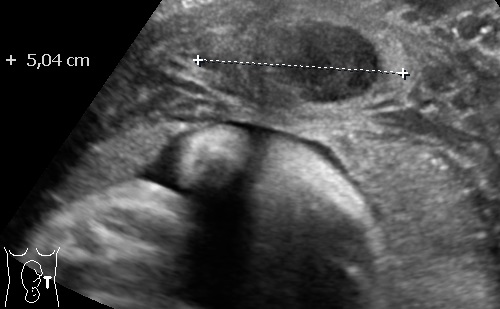

Multiple Myomas in pregnancy 1